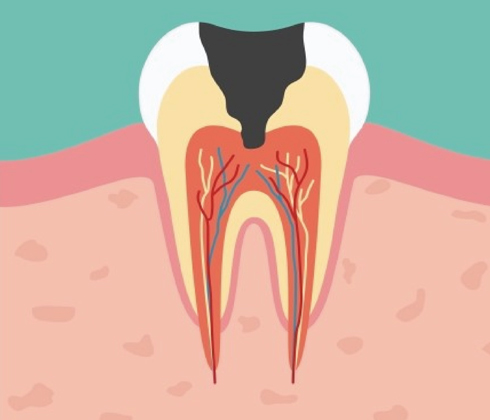

방치된 충치의 진행속도는 매우 빠릅니다.

단계가 진행 될 수록 치아 삭제량이 더 많아집니다.

단계가 진행 될 수록 치료 비용이 더 비싸집니다.

단계가 진행 될 수록 치료기간이 더 길어집니다.